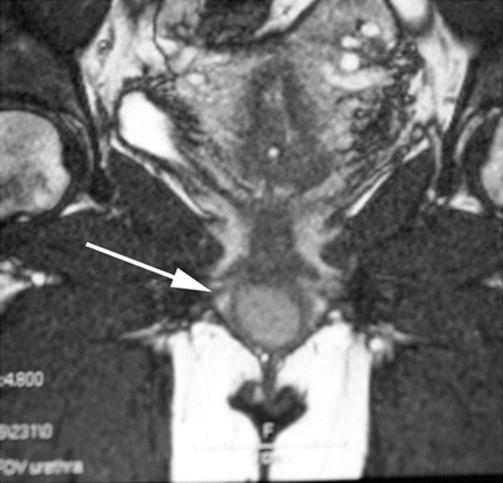

Fig. 8.28

A sagittal T2 MRI image showed a clear-fluid cystic mass of the anterior vaginal wall

Fig. 8.29

A superior and inferior flap of the anterior vaginal wall was created to expose the cystic area. The mass was excised superficially to the perivesical fascia